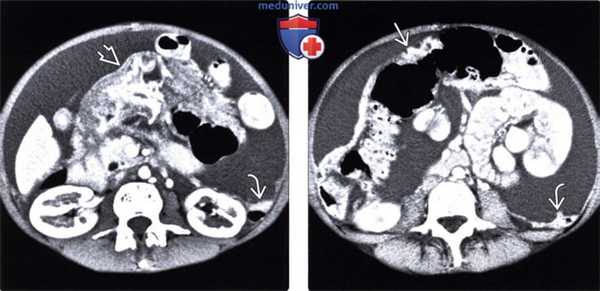

(Слева) На аксиальной КТ с контрастным усилением определяется выраженное утолщение дистальных отделов желудка, которое может быть обусловлено злокачественным новообразованием. Выраженный асцит сочетается с узловым утолщением париетальной брюшины что является признаком злокачественной природы асцита в результате первичного рака желудка.

(Справа) На аксиальной КТ с контрастом у этого же пациента визуализируется опухоль, распространяющаяся по ходу желудочно-ободочной связки, и поражающая поперечную ободочную кишку. Обратите внимание на локальное узловое утолщение париетальной брюшины. Опухоли ЖКТ часто становятся причиной «злокачественного» асцита у мужчин.